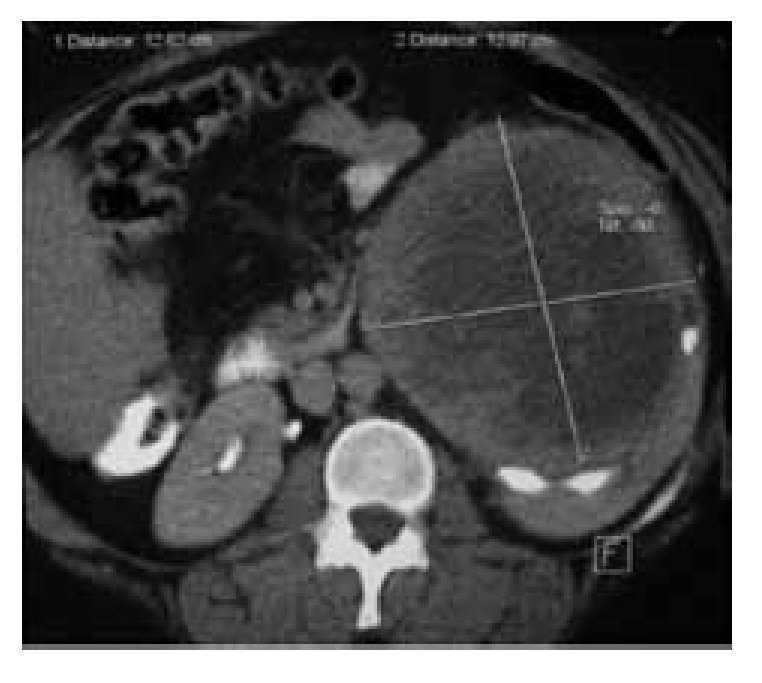

Paciente femenina de 37 años, padre hipertenso. Fumaba 1 a 2 cigarros al día desde hacía 10 años, consumo ocasional de alcohol. Hipertensión arterial de recién diagnóstico controlada con captopril. Acudió por sensación de masa en fosa renal izquierda de 3 meses de evolución no asociado a dolor, pérdida de peso o hematuria. A la exploración física con tensión arterial de 120/90 mmHg, abdomen blando, depresible, presencia de masa firme palpable en flanco izquierdo, no dolorosa. Laboratorio con Hb: 14.3g/dL, creatinina: 0.73 mg/dL, pruebas de funcionamiento hepático y radiografía de tórax normales. Tomografía computadorizada: masa sólida 12 x 12 cm dependiente de riñón izquierdo, con áreas de necrosis y calcificaciones (Imagen1). Se realiza nefrectomía radical izquierda. Se identifica tumor de 20 x 15 x 10 cm dependiente de polo inferior (Imagen 2).

Imagen 1. Tomografía computadorizada: masa sólida 12 x 12 cm dependiente de riñón izquierdo, con áreas de necrosis y calcificaciones.